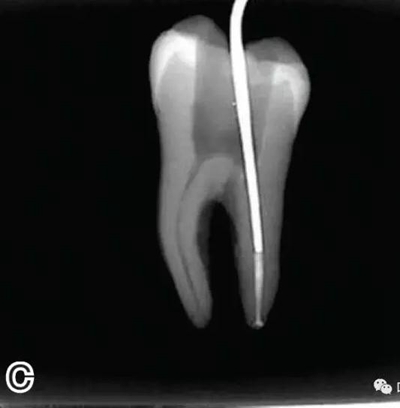

3、試尖

選擇非標(biāo)準(zhǔn)牙膠尖(如0.04、0.06 錐度牙膠尖)作為主尖,型號一般與根管預(yù)備最大號的器械型號一致,能到達(dá)距根尖0.5~1 mm 處,主尖尖段與根管壁緊密接觸。拍試尖X 線片進(jìn)行確認(rèn)(圖3)。

圖3 試尖,A.試主尖 B.拍試尖X片